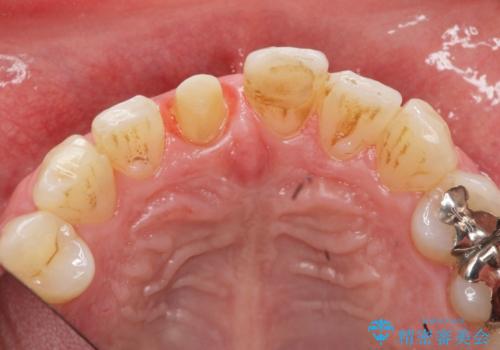

前歯の変色を改善!セラミック治療

- 前歯の変色が気になり審美障害の改善を求めて来院されました。

根管治療に伴う歯の色調変化はよく見られる所見です。

セラミッククラウン製作を行い審美性の改善を計画します。

周囲の歯の色調に合わせた、自然なセラミック治療を行うことができましt。